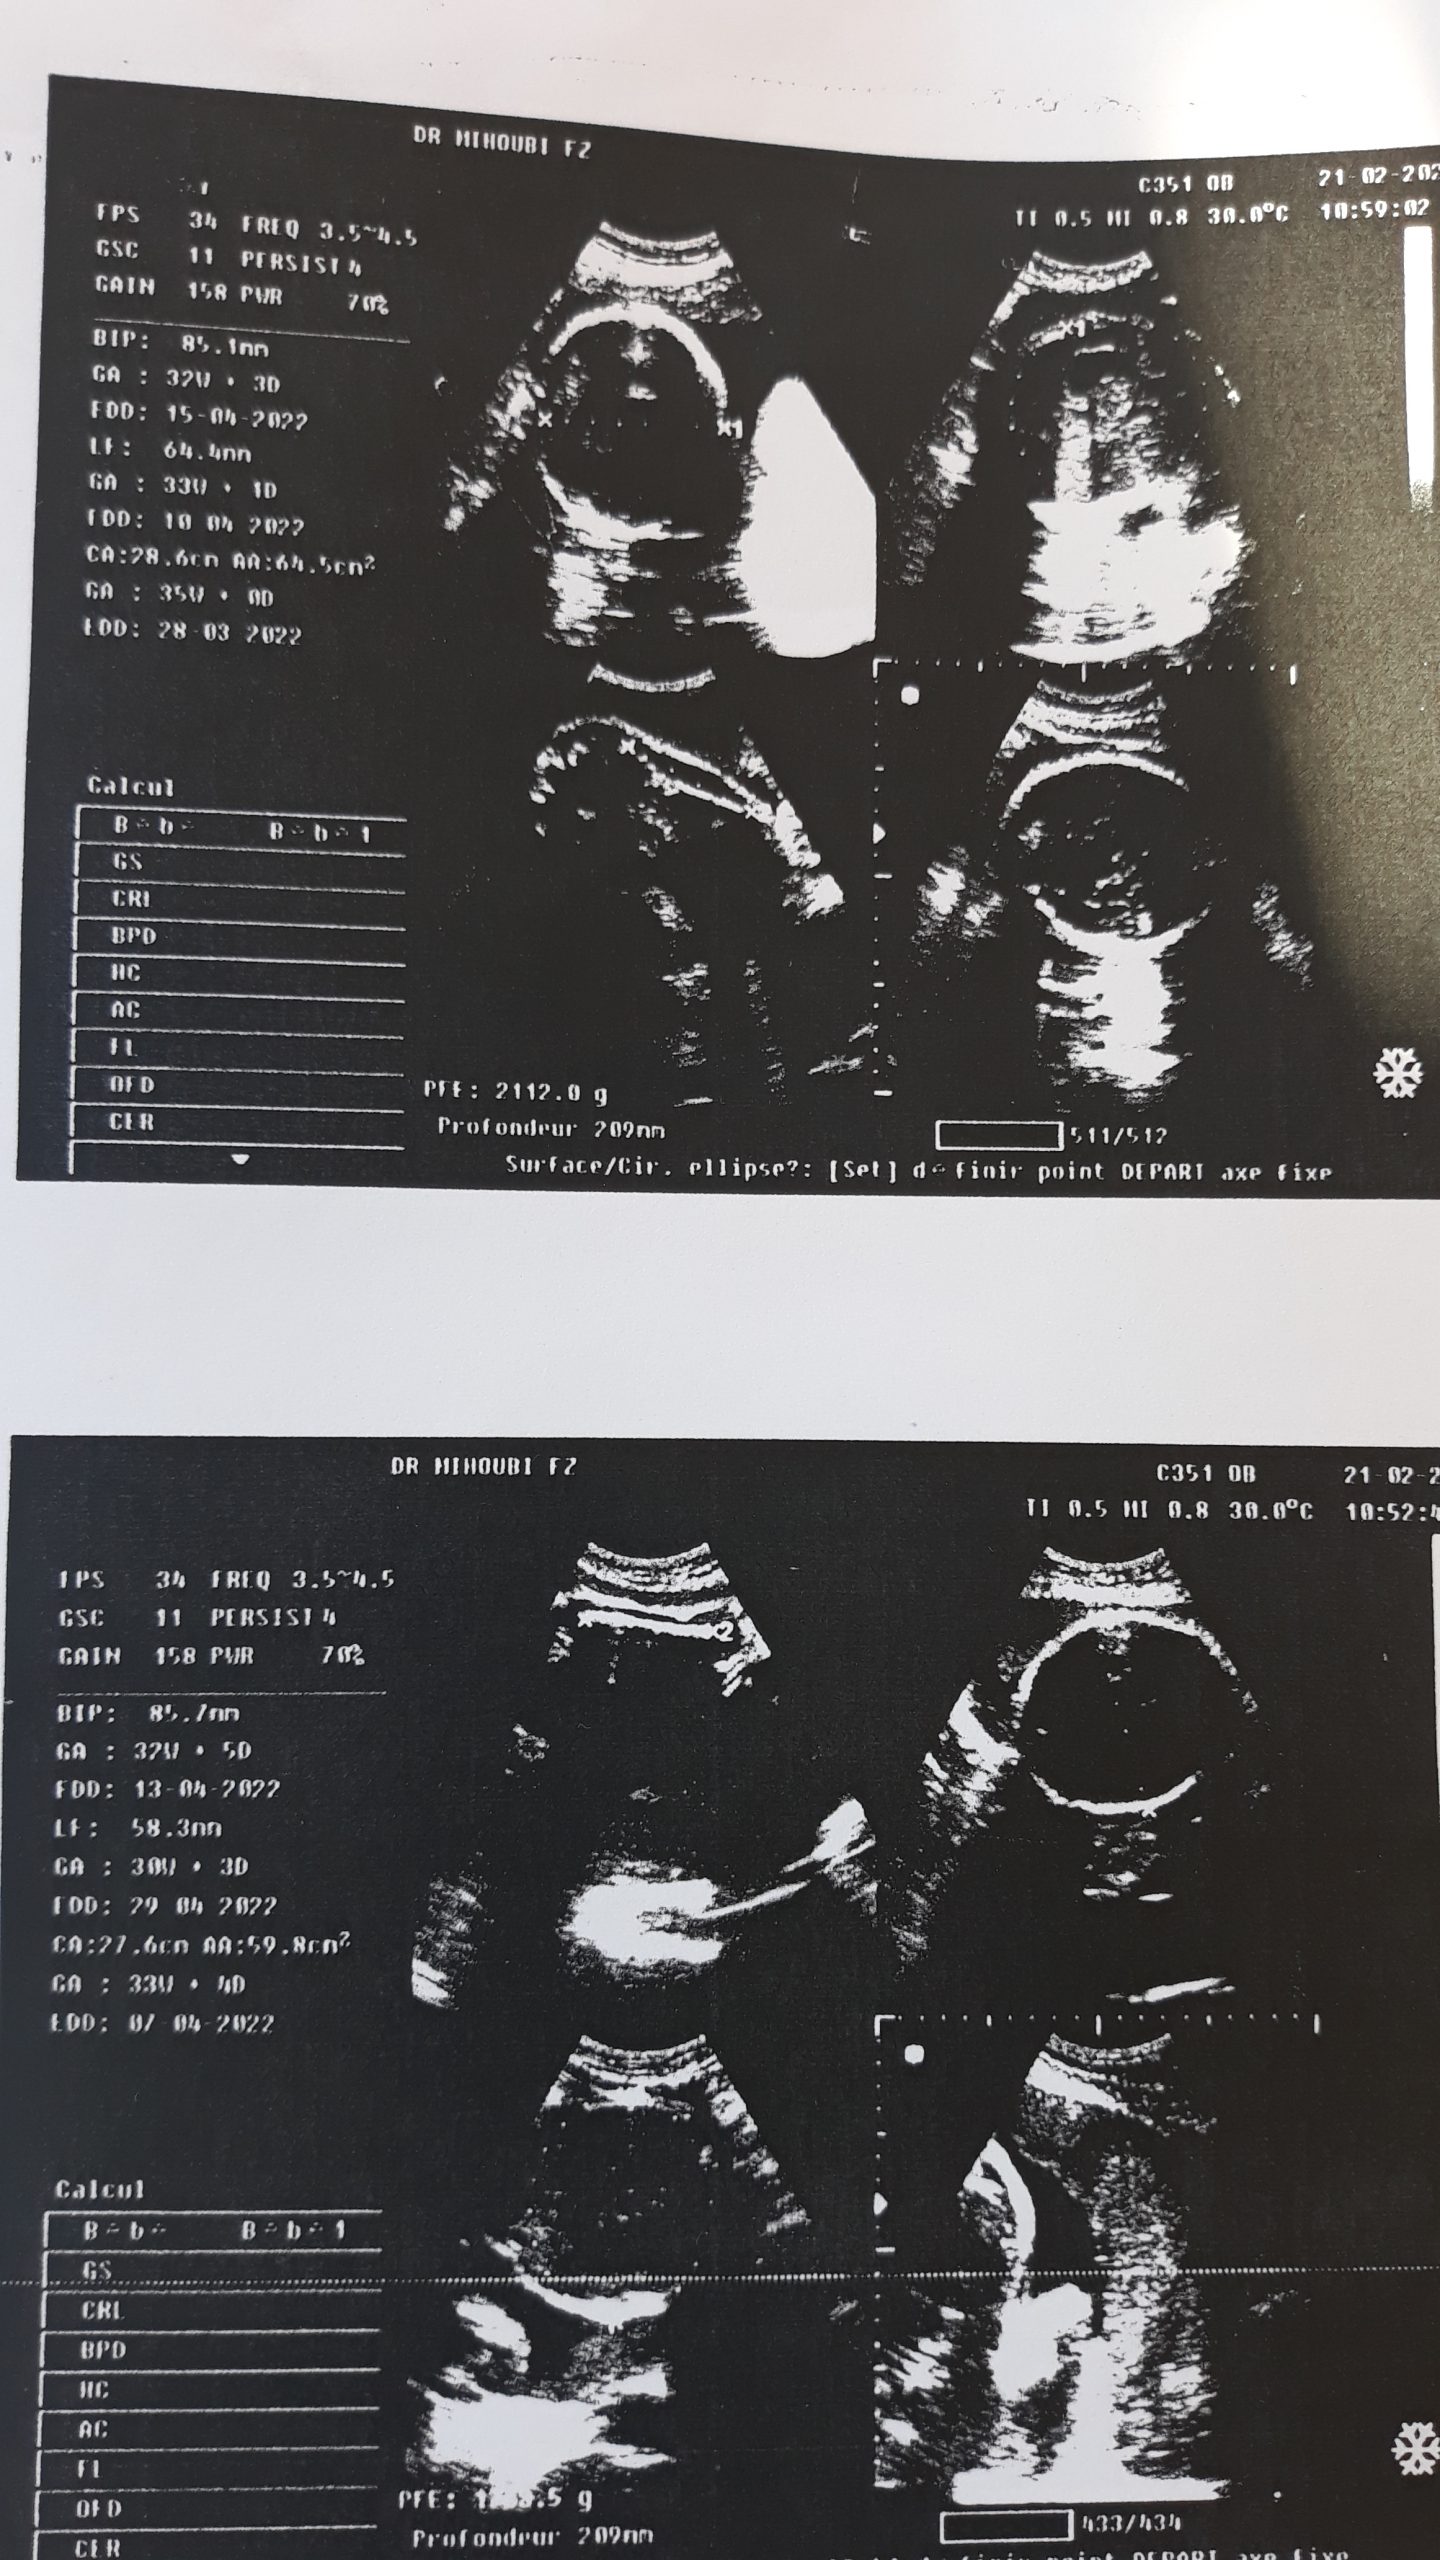

“شامي رقية” والدة الرضيع المختطف، أكدت في حديثها لـ “النهار” أنها ذهبت لعدة أطباء لمتابعة حملها، وكل الأطباء أكدوا أنها حامل بتوأم من جنس ذكر، وعند دخولها للعيادة وملء البيانات وإجراء العملية القيصرية، شاهدت الأم طفلاها وهي على طاولة العمليات، وبعدها نقلت لغرفتها، لتتفاجأ بطفل واحد فقط، لتدخل في حالة “هستيريا” كبيرة، كيف لا والرضيع الثاني والذي تمت تسميته “عبيدة بن الجراح” لا يوجد بجانب أخيه في السرير الذي بجانبها داخل العيادة.

يحدث هذا في انتظار ما ستفسر عنه التحقيقات الأمنية وكذا العدالة الجزائرية المتواصلة لحد الآن، بعد مرور أزيد من 4 أشهر عن الواقعة، فيما ناشدت عائلة “قويسي”، السلطات العليا في البلاد، إيفاد لجنة تحقيق إلى العيادة من أجل إرجاع الطفل إلى ذويه، في ظل توفر كل الإثباتات الطبية بأن الأم “شامي رقية” زوجة “قويسي ماجر” كانت تحمل في بطنها توأما.